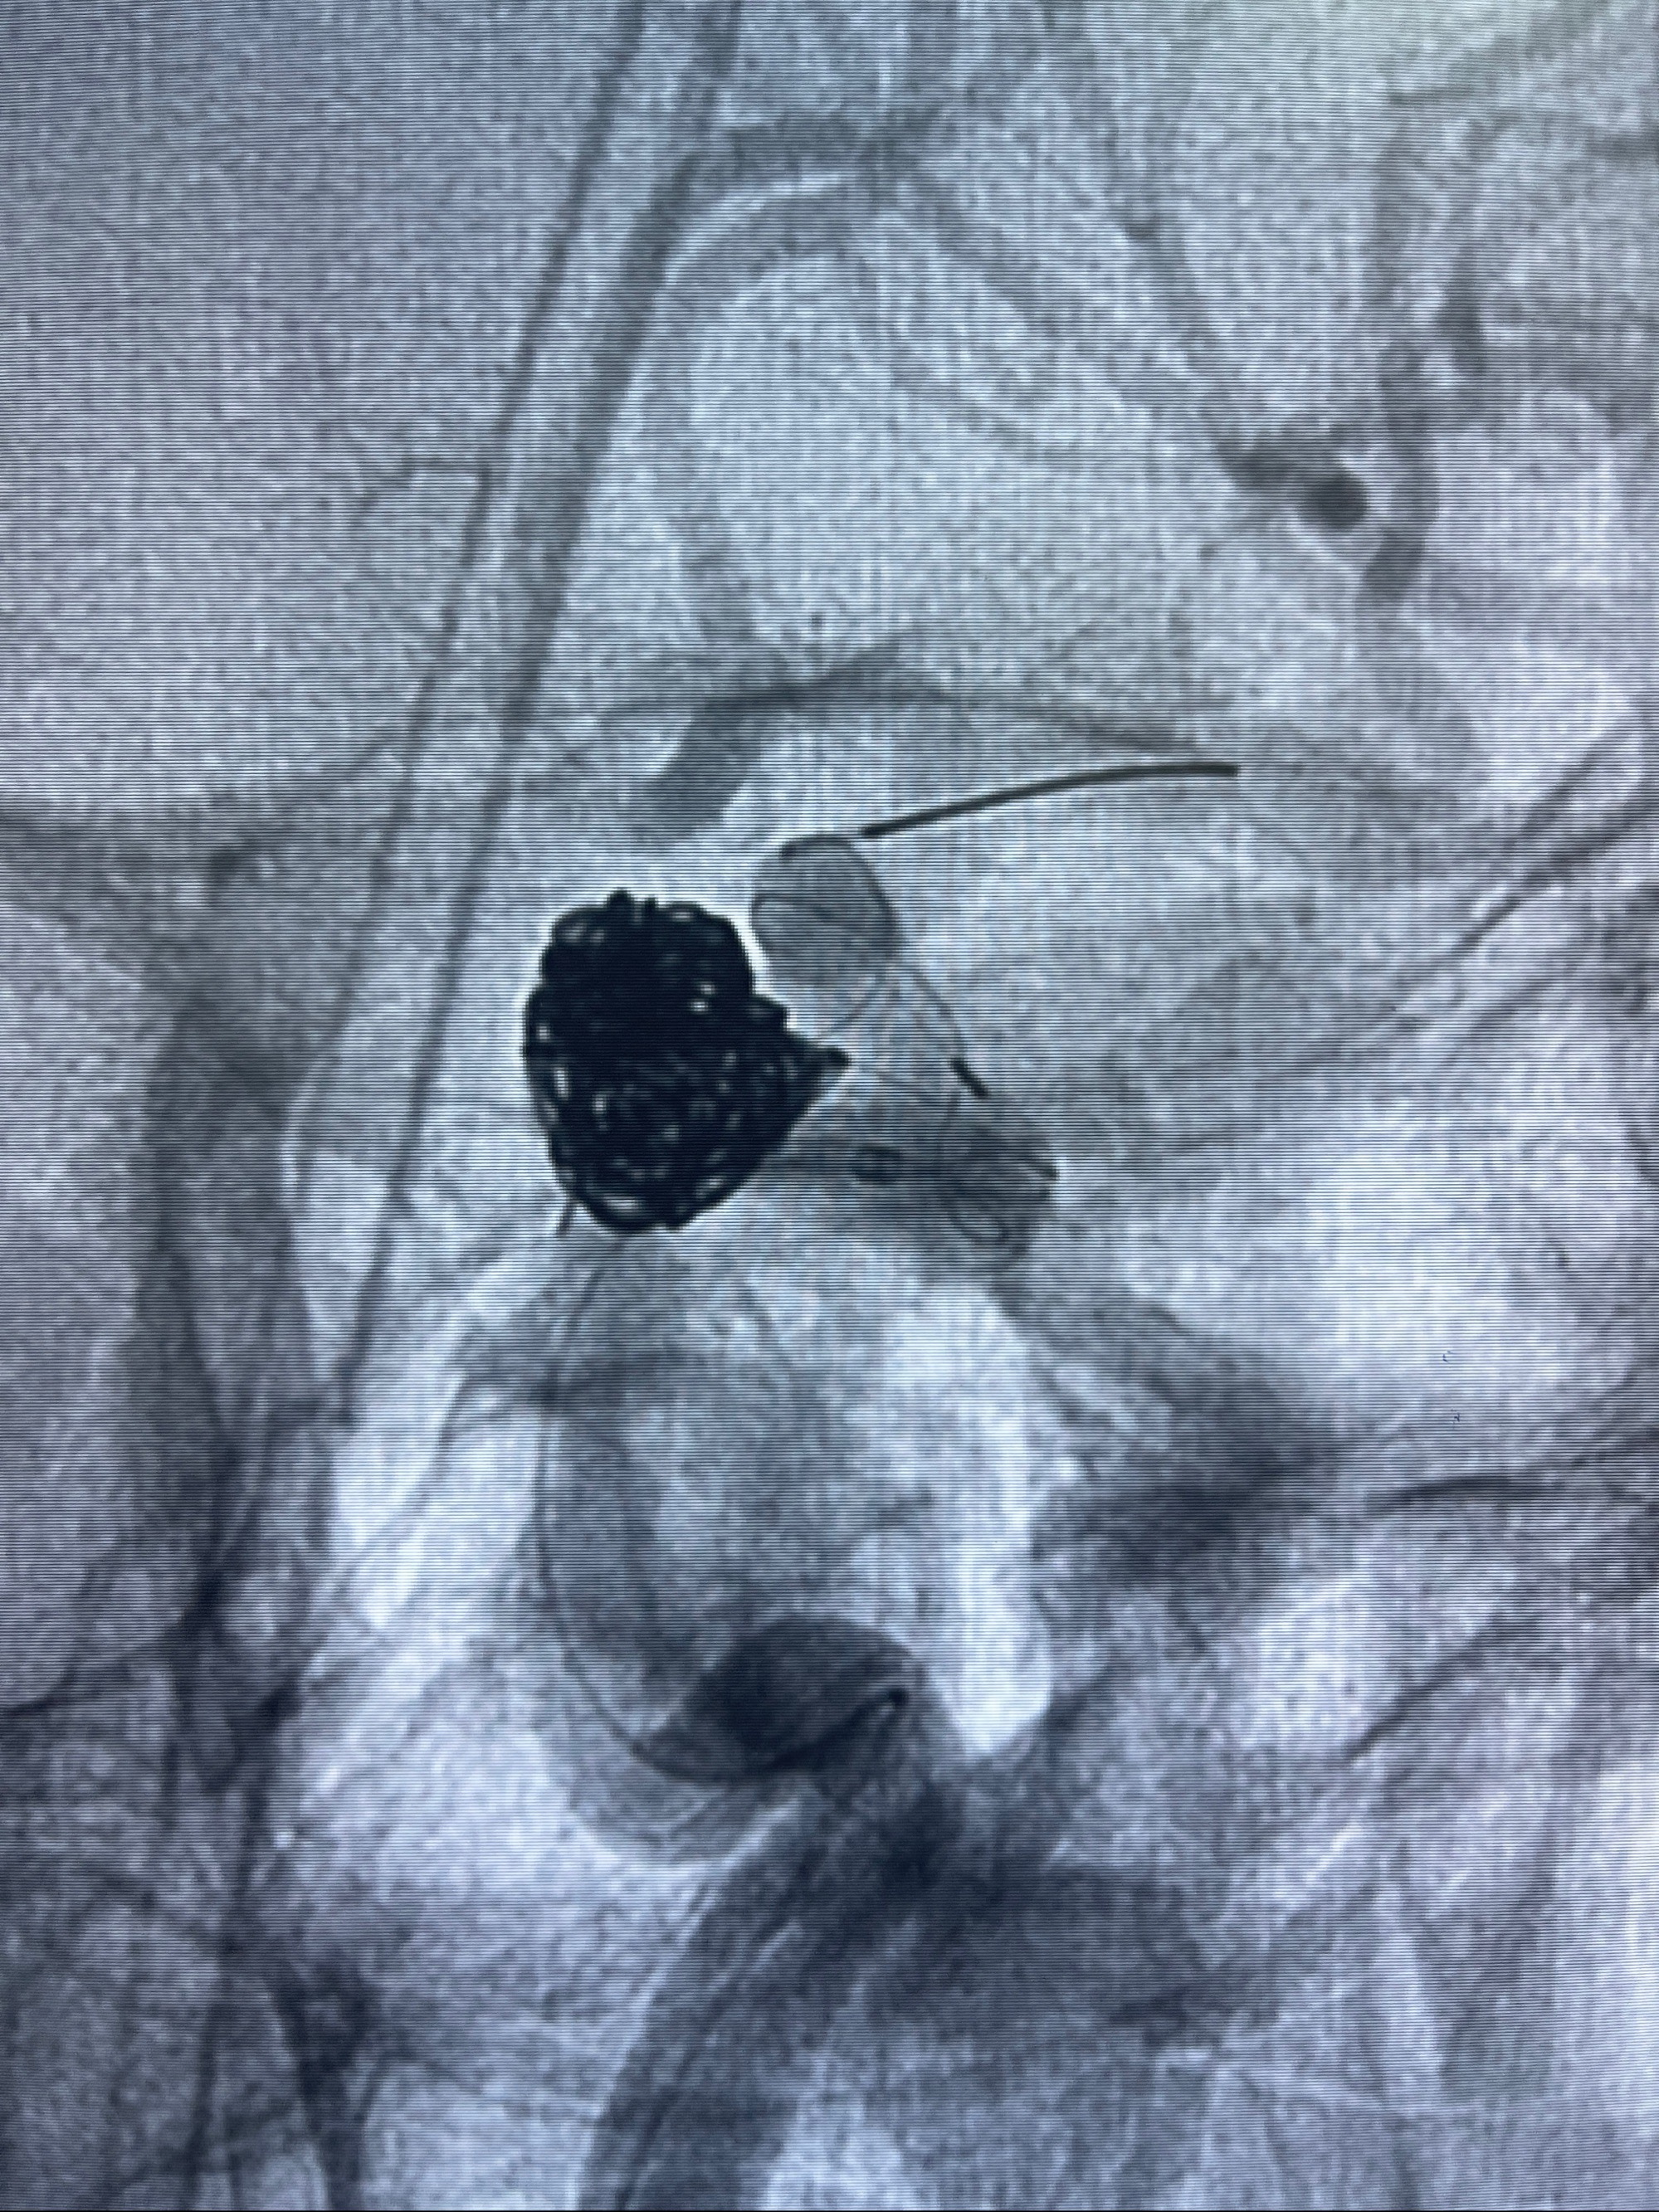

- Tubridge 4.0-20mm密网支架

- 加奇微弹簧圈:7*30/6*20/5*20/2*8

术后3D显示支架贴壁佳